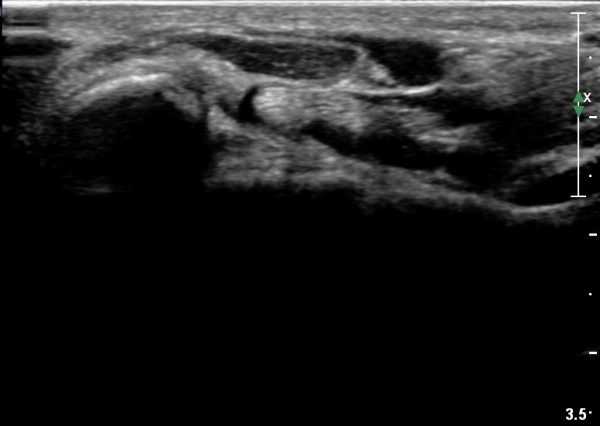

ÃÊÀ½ÆÄ °Ë»ç

¼Õ¸ñÀÇ È¾´Ü¸é°Ë»ç¿¡¼­ Á¤Á߽ŰæÀÇ ºÎÁ¾ µî ƯÀÌ ¼Ò°ßÀÌ º¸ÀÌÁö ¾Ê´Â´Ù(»çÁø 1).

¼ö±Ù°ü ±ÙÀ§ºÎ Ⱦ´Ü¸é°Ë»ç¿¡¼­ Á¤Á߽ŰæÀÇ ºÎÁ¾ µî ƯÀÌ ¼Ò°ßÀÌ º¸ÀÌÁö ¾Ê´Â´Ù(»çÁø 2).

¼ö±Ù°ü ¿øÀ§ºÎ Ⱦ´Ü¸é°Ë»ç¿¡¼­ Á¤Á߽ŰæÀÇ ºÎÁ¾ µî ƯÀÌ ¼Ò°ßÀÌ º¸ÀÌÁö ¾Ê´Â´Ù(»çÁø 3).